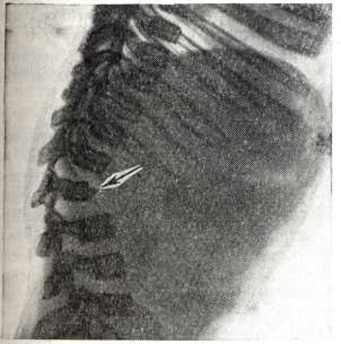

Рис. 4.

Рентгенограмма в боковой проекции нижних грудных и поясничных позвонков больного гаргоилизмом. Выраженный кифоз с вершиной угла на уровне LI — LII; тело LI позвонка уменьшено в размерах, передняя поверхность террасоподобно деформирована (указано стрелкой) за счёт недоразвития передне-верхнего угла.